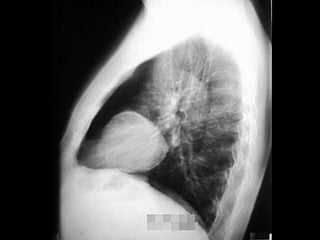

RADIOGRAFIA

• Radiografía normal

• Radiografía patológica

– Ensanchamiento mediastinal

• Técnica radiográfica

• Estructuras normales de tamaño o distribución atípica

• Estructuras vasculares

• Tumores